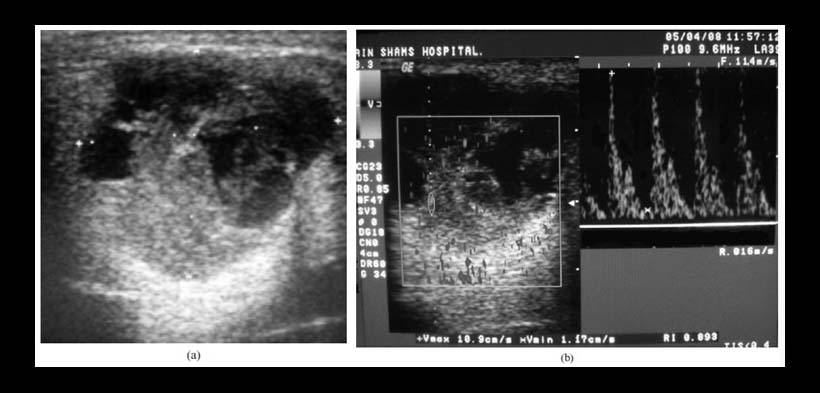

Fig. 1. (a) Ecografía en escala de grises (GSS) de la glándula parótida izquierda mostrando una masa lobulada bien definida hipoecoico homogéneo con refuerzo acústico posterior. (b) la ecografía Doppler a color (CDS) de la misma lesión que muestra Grado 1de  vascularización periférica, la ecografía Doppler espectral (SPD) muestra los mismos signos del flujo sanguíneo. El examen histopatológico reveló el diagnóstico de adenoma pleomórfico.